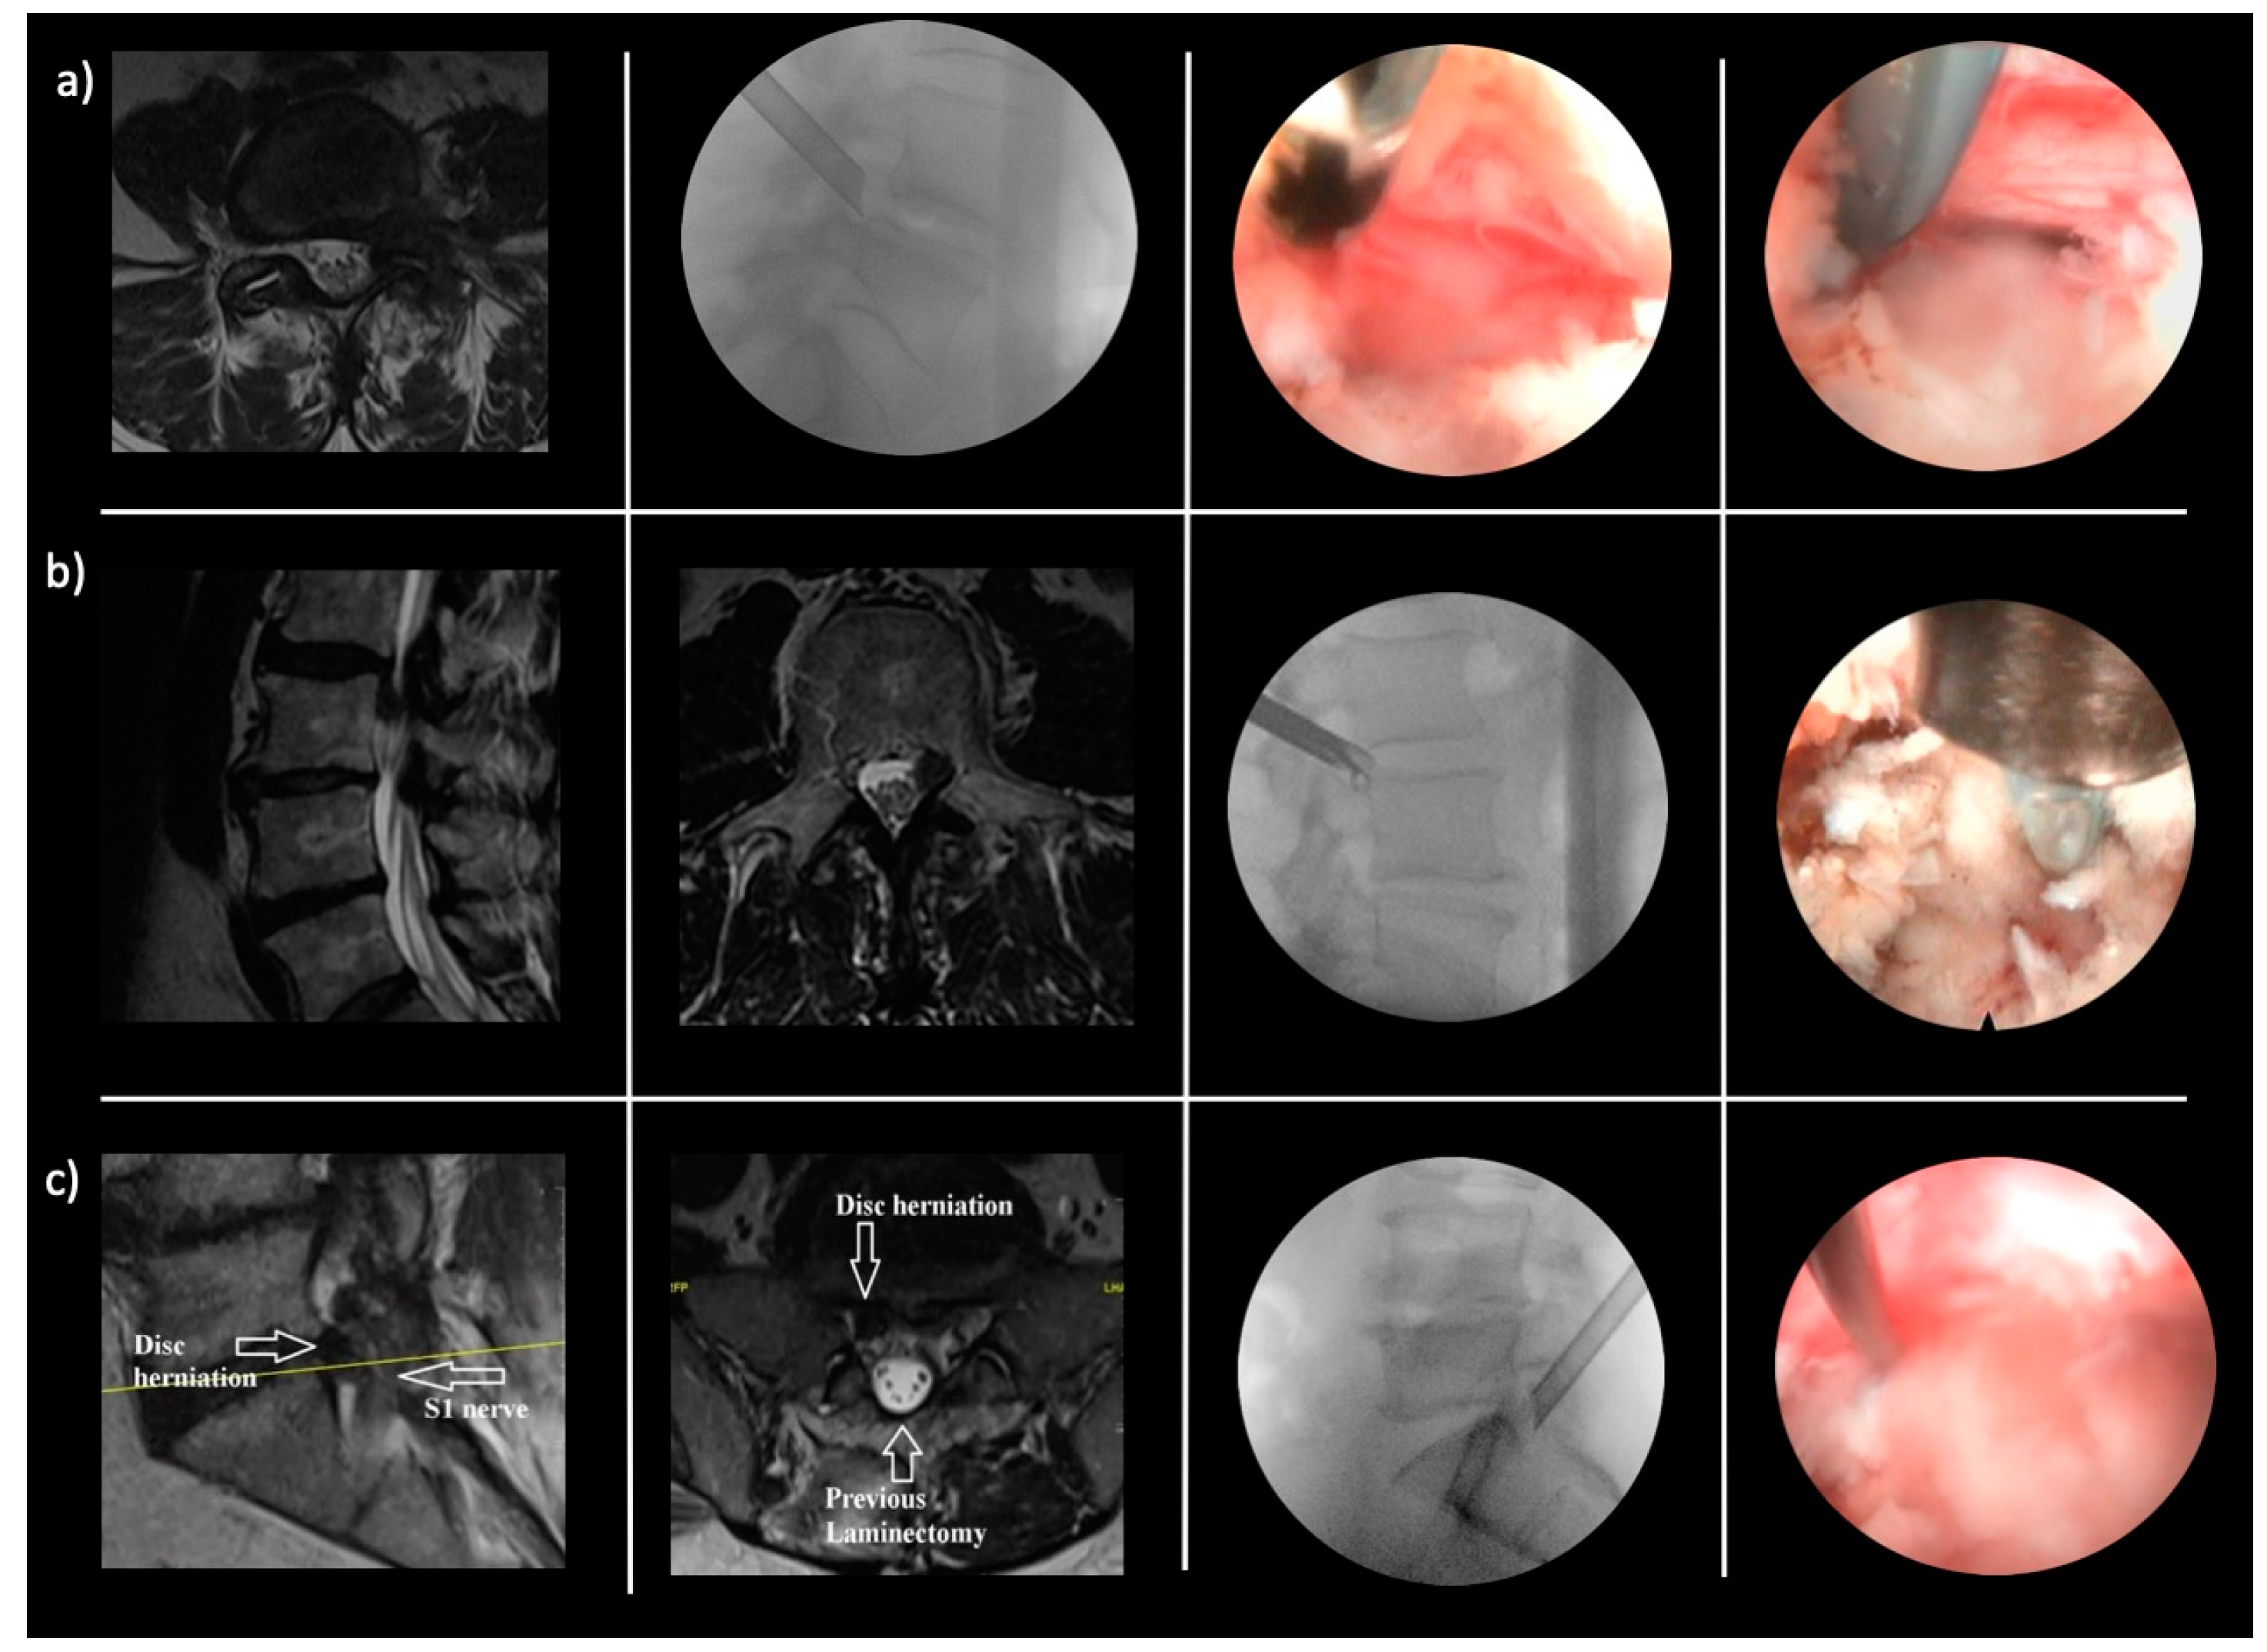

- Lewandrowski, K.-U.; Abraham, I.; León, J.F.R.; Telfeian, A.E.; Lorio, M.P.; Hellinger, S.; Knight, M.; De Carvalho, P.S.T.; Ramos, M.R.F.; Dowling, Á.; et al. A Proposed Personalized Spine Care Protocol (SpineScreen) to Treat Visualized Pain Generators: An Illustrative Study Comparing Clinical Outcomes and Postoperative Reoperations between Targeted Endoscopic Lumbar Decompression Surgery, Minimally Invasive TLIF and Open Laminectomy. J. Pers. Med. 2022, 12, 1065. [Google Scholar] [CrossRef]

- Yeung, A.; Roberts, A.; Zhu, L.; Qi, L.; Zhang, J.; Lewandrowski, K.-U. Treatment of Soft Tissue and Bony Spinal Stenosis by a Visualized Endoscopic Transforaminal Technique Under Local Anesthesia. Neurospine 2019, 16, 52–62. [Google Scholar] [CrossRef]

- Lewandrowski, K.-U.; Yeung, A. Lumbar Endoscopic Bony and Soft Tissue Decompression With the Hybridized Inside-Out Approach: A Review And Technical Note. Neurospine 2020, 17, S34–S43. [Google Scholar] [CrossRef] [PubMed]

- Yeung, A.; Lewandrowski, K.-U. Early and staged endoscopic management of common pain generators in the spine. J. Spine Surg. 2020, 6, S1–S5. [Google Scholar] [CrossRef] [PubMed]

- Lewandrowski, K.-U.; Dowling, Á.; de Carvalho, P.S.T.; Calderaro, A.L.; dos Santos, T.S.; Silva, M.S.D.L.E.; León, J.F.R.; Yeung, A. Indication and Contraindication of Endoscopic Transforaminal Lumbar Decompression. World Neurosurg. 2020, 145, 631–642. [Google Scholar] [CrossRef]